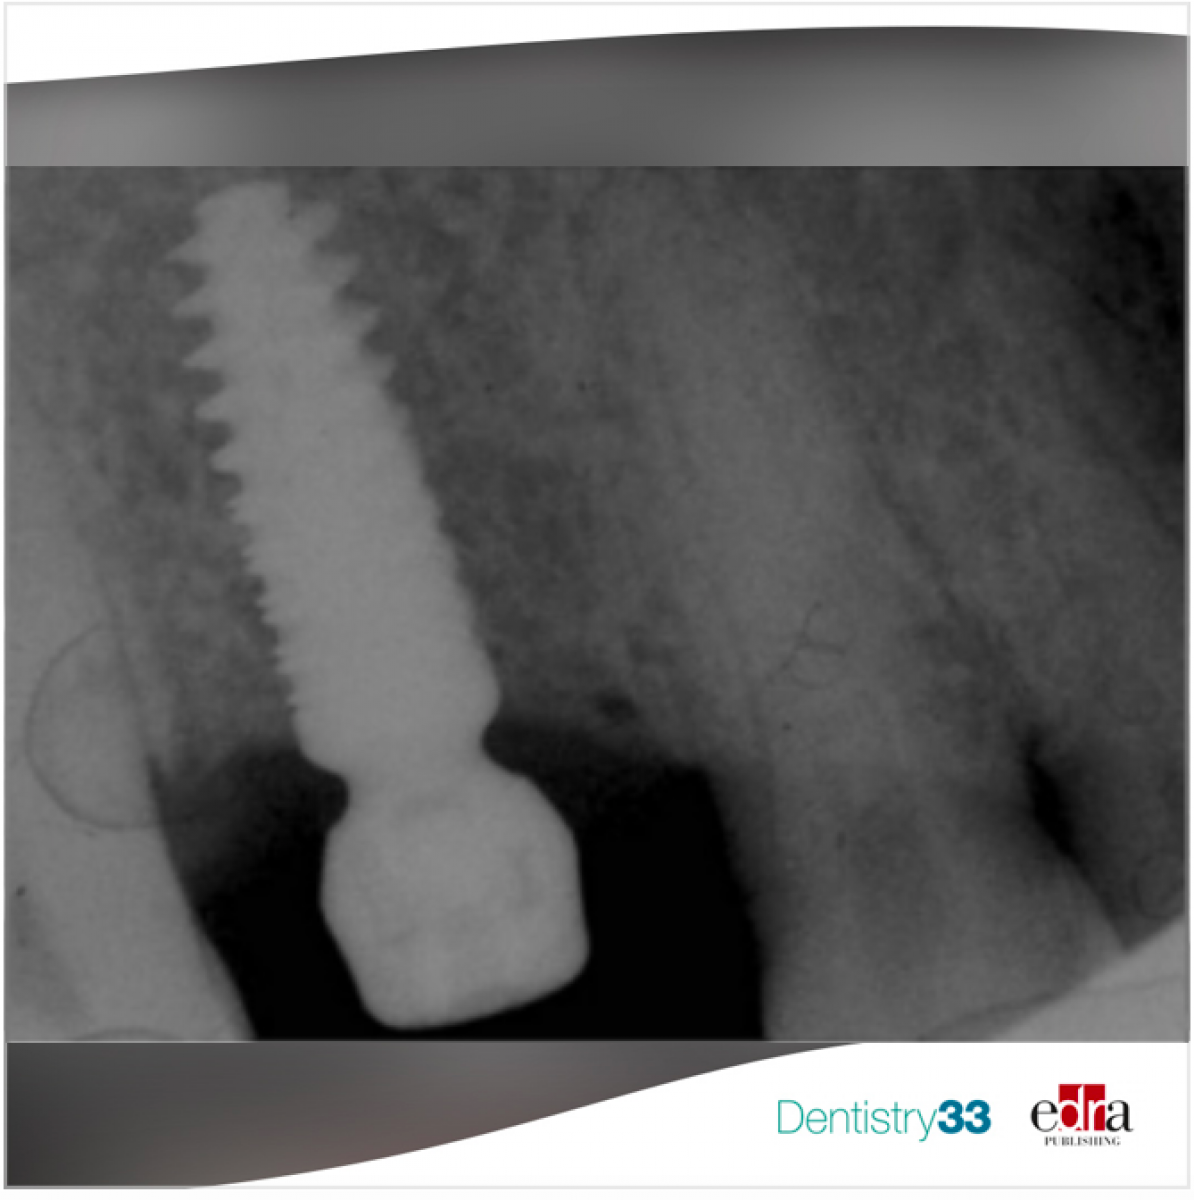

Correlation between Implantology and risk of bleeding in patient in chronic therapy with antithrombotic drugs

and antithrombotic therapies if adequate local haemostatic solutions are used. On the contrary, the literature is scarce on giving indications on the procedures to be adopted in case of dental implant surgery (both single and multiple implants, bone grafts, sinus lift procedures) in patients taking AP, OAC and DOAC, given that these interventions should be considered procedures with a high risk of bleeding in patients on antithrombotic therapy.

In the systematic review conducted by Bajkin et al, the authors evaluated the risk of bleeding in dental implant procedures in patients taking antiplatelet drugs (AP), oral anticoagulants (OAC) and direct oral anticoagulants (DOAC).

Nine studies were included in the review. Postoperative bleeding occurred in 10 (2.2%) of the 456 cases that required implant placement; in all these cases, bleeding was controlled with the use of local hemostatic agents. The incidence of bleeding in patients taking antiplatelet drugs it was found to be 0.4%. Among those taking oral anticoagulants, the incidence of bleeding was 5.7% and among those taking direct oral anticoagulants, the incidence of bleeding was 3.3%. The number of more extensive surgical procedures (i.e., sinus lift and bone graft procedures) was limited, and often no further information was provided on the surgery, specific antithrombotic administered or bleeding, so it was not possible. perform a further analyses.

From the data emerging from this review, which must be confirmed by other similar reviews, it can be concluded that OAC, DOAC or AP drugs should not be suspended in anticipation of implant surgery as the risk of bleeding is very low and well controllable through local hemostats.